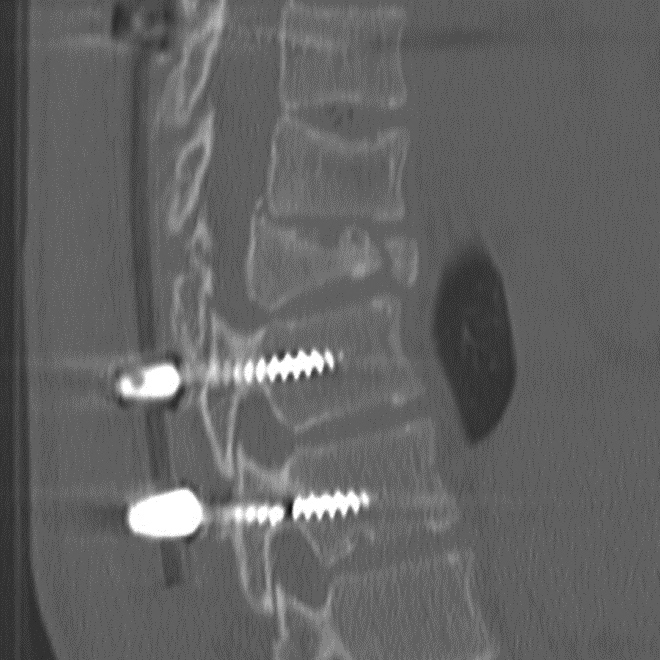

Just as with the immediate post-operative setting, CT is the modality of choice for evaluating complications related to spinal fusion. Screw fracture may occur in up to 25% of patients (Figure 13) (Ohashi, 2009; Lonstein, 1999). As with all cases of hardware failure, the imaging findings should be correlated with patient symptoms as not all hardware complications relate to current clinical symptoms. CT can be useful for the detection of polyethylene dislocation, which may occur in shoulder, hip and knee arthroplasties, and may be difficult to detect on radiographs (Figure 14) (Clarke, 2004).

Hardware Failure. Sagittal multiplanar reformation demonstrates fractured pedicle screw in patient with treated vertebral compression fracture and sudden onset of worsening back pain.